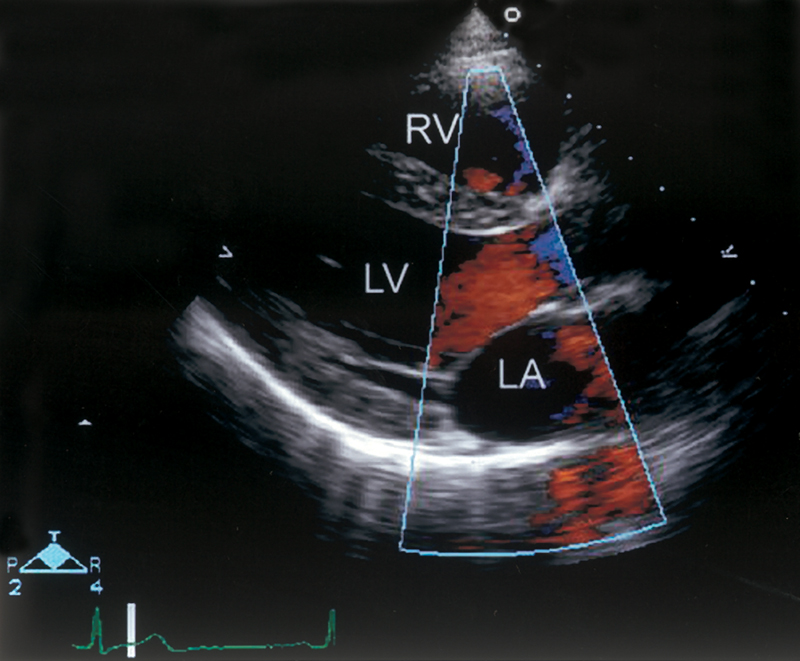

فحوصات تشخيصية لبعض امراض القلب والشرايين التاجية